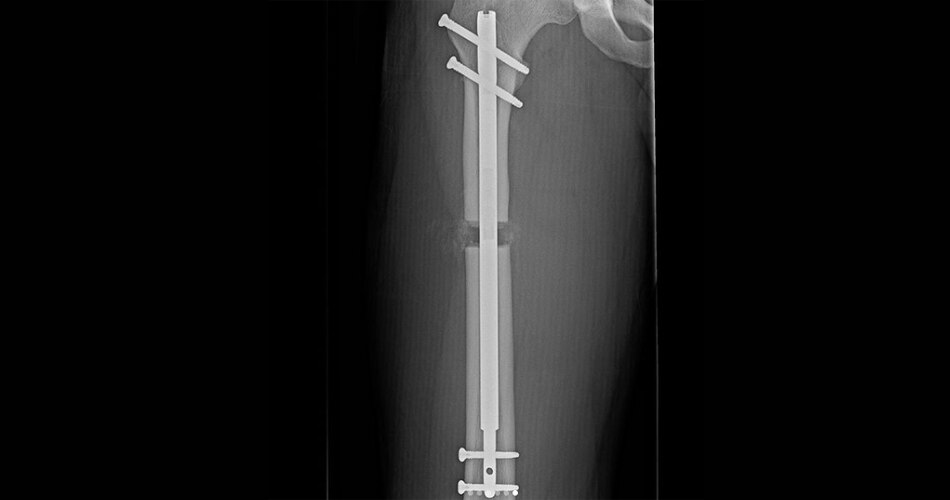

फ्लोर्स के सर्जरी के पहले और बाद की तस्वीरें सोशल मीडिया पर वायरल हैं. तस्वीरों में फ्लोर्स की बढ़ी हुई लंबाई साफ देखी जा सकती है. डॉक्टर देबीप्रशाद ने याहू लाइफस्टाइल को बताया कि इस सर्जरी में जांघ या निचले पैर की हड्डी को लंबा किया जाता है.

इस प्रक्रिया में 6 इंच तक लंबाई बढ़ाई जा सकती है. फ्लोर्स ने कहा, 'मुझे पता है कि 5'11 एक अच्छी हाइट है और बहुत से लोग इतना लंबा होना पसंद करते हैं लेकिन मैं इससे थोड़ा अधिक चाहता था और अपनी जितना संभव हो अपनी एथलेटिक क्षमता बढ़ाना चाहता था.'